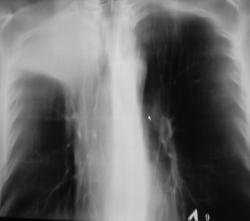

Иллюстрации 4, 5. На обзорной рентгенограмме органов грудной полости, произведенной в прямой проекции, в дополнении к скиалогической картине, полученной при цифровой флюорограмме добавлено — некоторое смещение верхнего средостения вправо с учетом смещения «просвета трахеи». При детальном исследовании области правого корня дополнительной информации не выявлено.